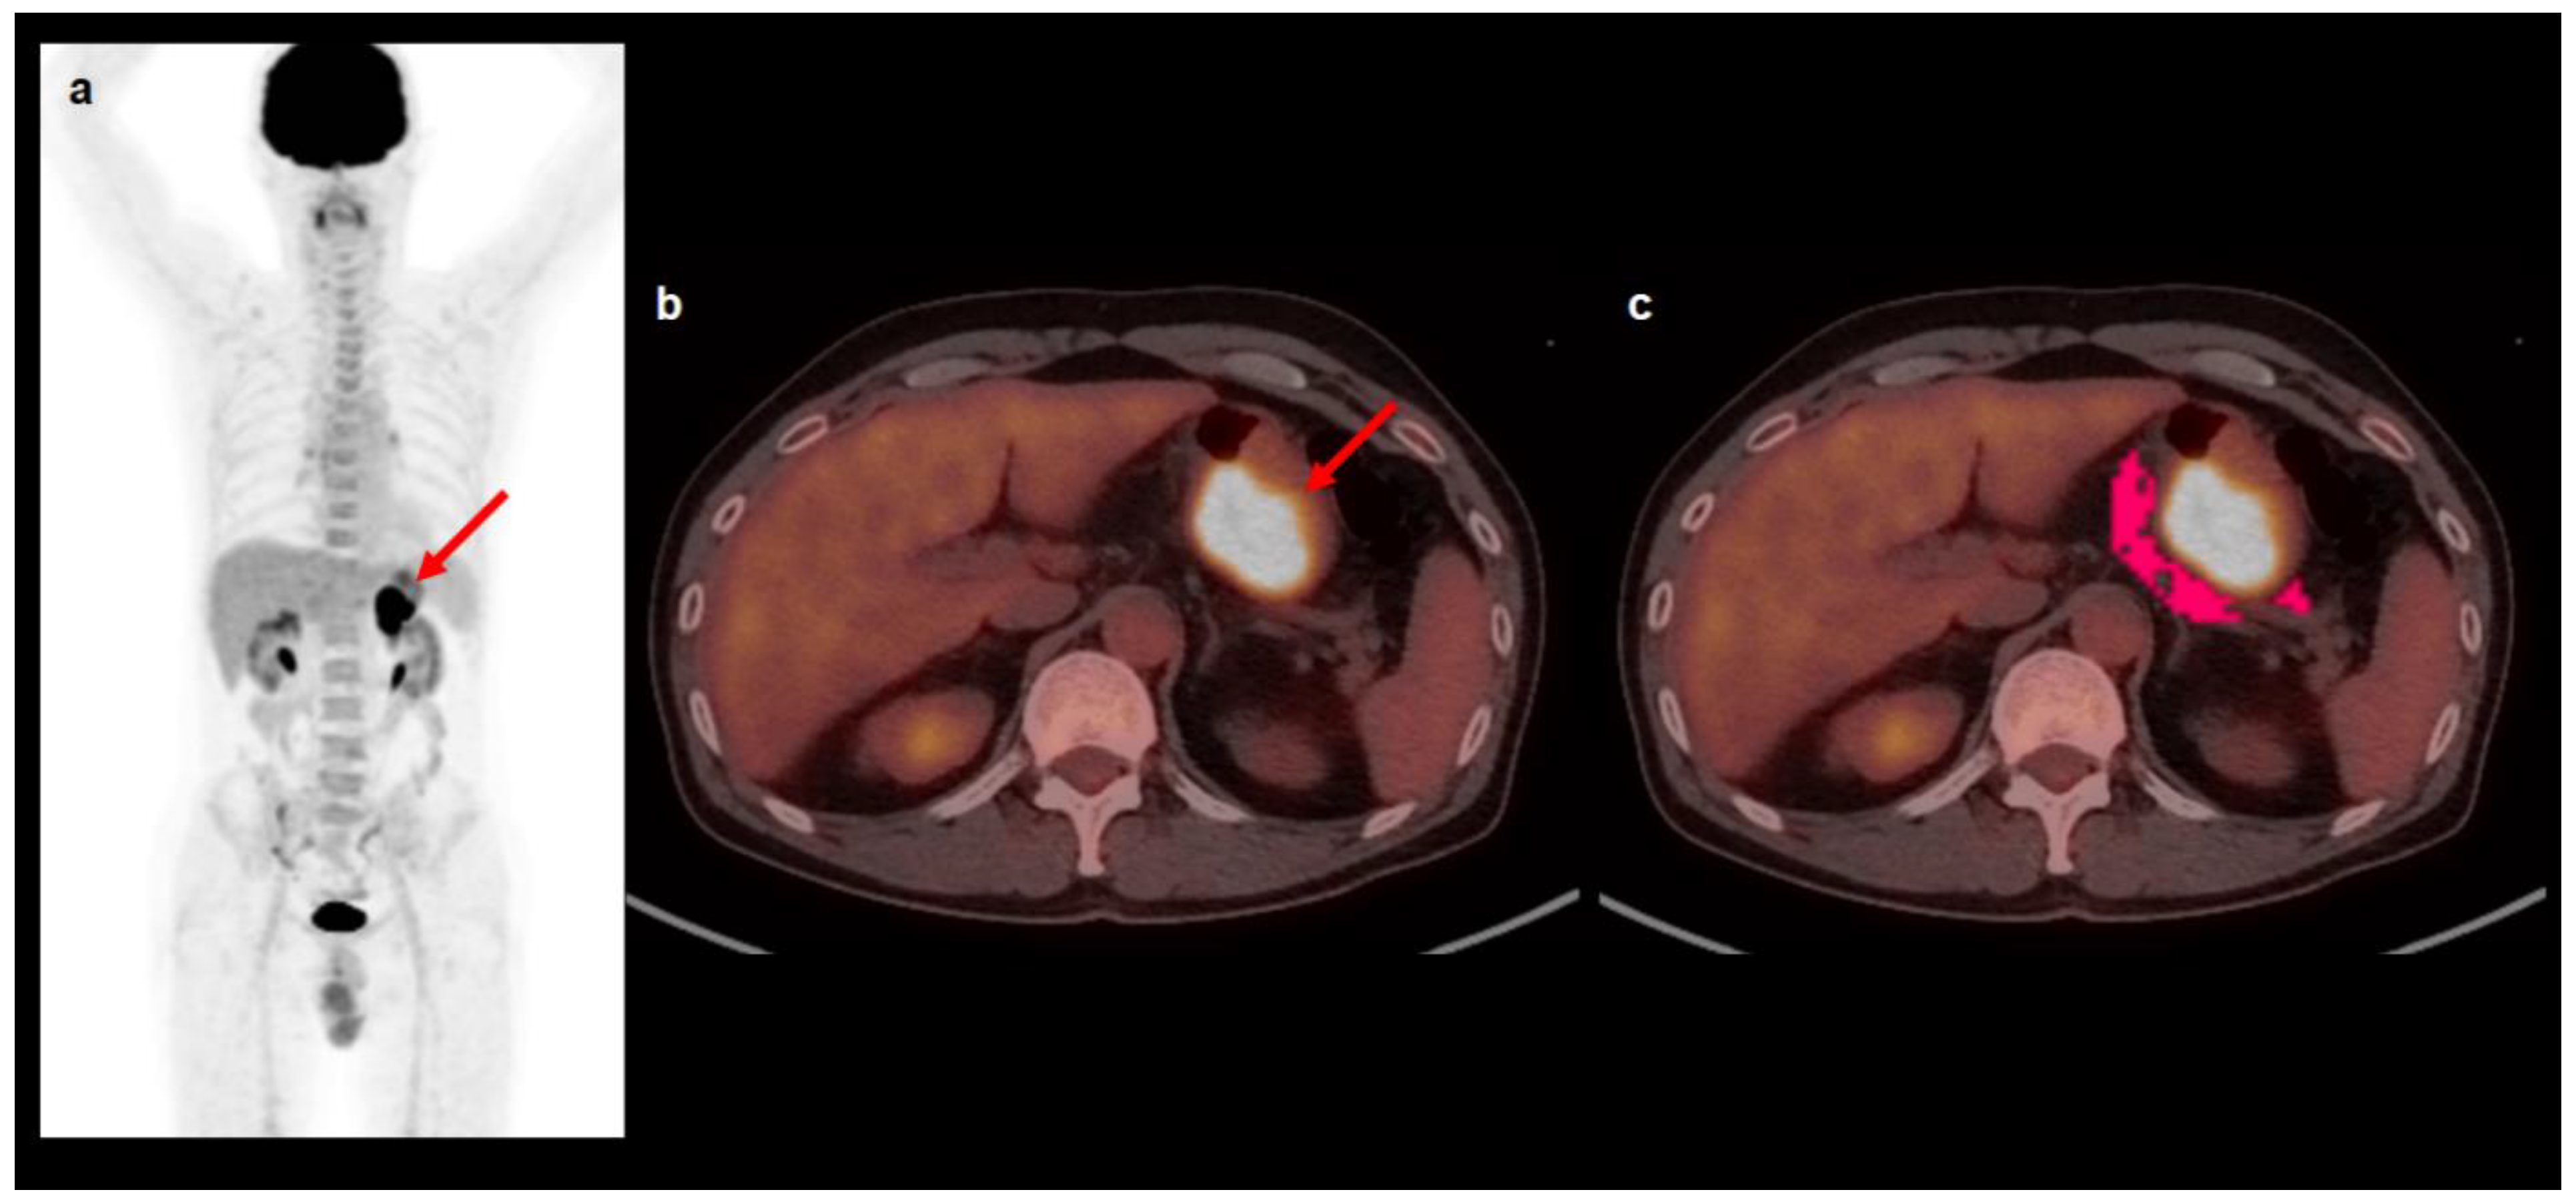

4.2. [18F]FDG PET/CT and Image Analysis